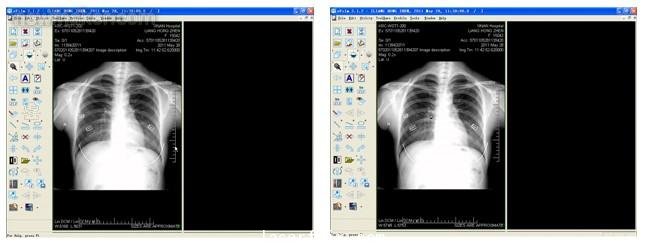

同時,由于現在的B超機很多也帶有VGA接口,用專業的VGA圖像采集采集的圖像質量非常高,在行業的應用中也得到用戶的普遍認可。如下圖所示,根據客戶要求抓取客戶計算機VGA屏幕輸出的CT以及X光機圖片,其中使用的采集設備是維視圖像研發生產的MV-VGA200采集卡,采集分辨率1024*768,刷新率60HZ。采集的圖像細節好,字跡清楚,對比度高,便于醫生辨別病變,用于光片輸出大屏顯示以及醫療圖像處理分析。

上述VGA采集卡的應用實例中,頭部是CT影像、胸部是X光影響,這些用于醫療工作站的原始采集設備也是維視圖像研發生產的MV-M1000/M2000高端黑白采集卡,該系列產品已經廣泛用于采集高頻的CT、X光機、核磁等非標準醫療設備中。維視圖像有多年的醫療圖像采集解決方案的提供經驗,可為用戶提供優質的視覺解決方案。